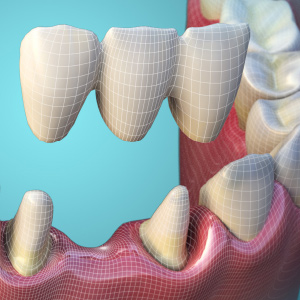

Advancements in Zirconia Block Technology

Tuesday, December 26, 2023

Thanks to the latest materials, there has never been a better time for dental practices to offer their patients quick and convenient chairside restorations. The fabrication of crowns and bridges can be optimized for beauty, strength, and speed. Also, the latest multi-layered pigmentation technology ...